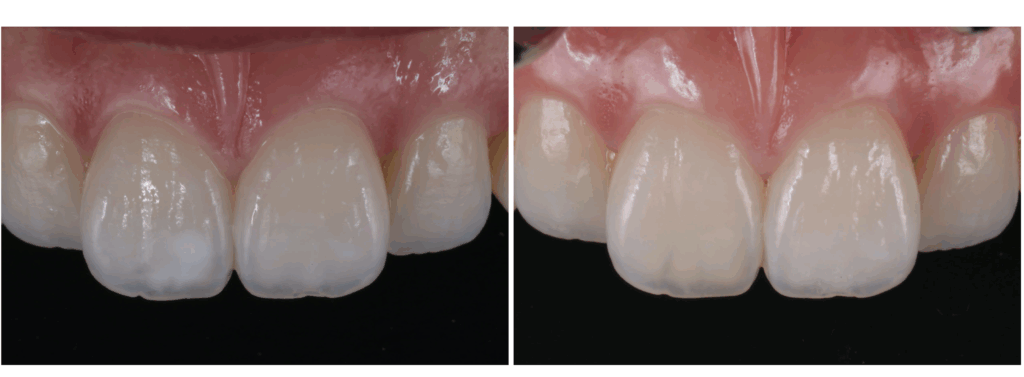

ブラウンスポットはホームホワイトニングで、白濁はICONで改善した症例のご紹介

【削らない・歯を守る審美治療】

「歯の表面にある**茶色い点(ブラウンスポット)と、前歯に広がる白く濁った模様(ホワイトスポット・白濁)**が気になって…」

このようなお悩みで、墨田区・江東区・中央区エリアから…